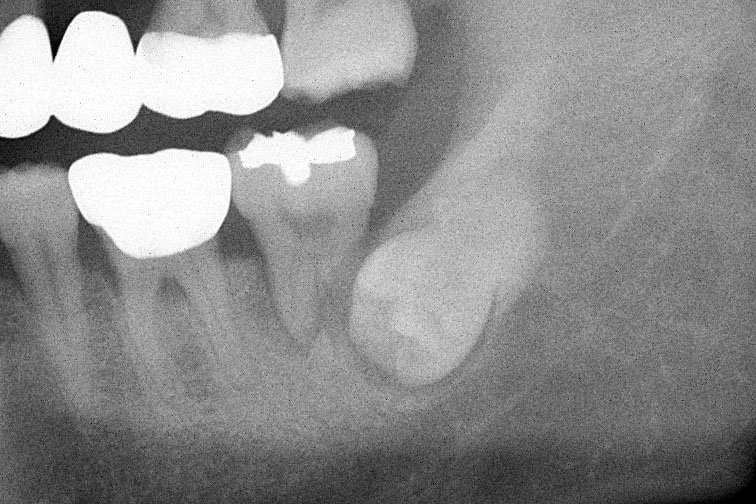

사랑니 발치

사랑니 주변에는 위험한 구조물들이 근접해 있습니다.

사랑니가 맹출하면서 불편감을 느끼거나 인접 치아에 손상을 줄 가능성이 높은 경우에는 발치를 고려해야 합니다. 그러나 사랑니 주변에는 하치조신경이나 상악동과 같은 손상되면 합병증이 발생하는 해부학적 구조물이 존재하기 때문에 수술전 정확한 진단이 필요합니다.

이처럼 사랑니 발치는 치과 소수술이기 때문에 구강외과전문의에게 진료를 받으시는 것이 수술 후 합병증 발생을 최소하하는 방법입니다.

사랑니 발치를 하고 싶어요. 과정이 어떻게 되나요?

사랑니 발치는 환자분의 사랑니 매복 상태를 확인해야 합니다. 타 병원에서 이미 x-ray를 촬영한 경우에는 카카오톡으로 올려주시면 원장님께서 확인하는 대로 발치가 가능한지 답을 주실 것입니다. x-ray가 없다면 일단 내원하셔야 정확한 상담이 가능합니다.가락삼성치과에서는 구강외과 국가전문의가 진료하고 있으며 대부분의 사랑니 발치는 가능합니다.

단, 사랑니가 신경을 손상시킬 가능성이 높은 경우, 환자분께서 불필요한 위험성을 감수할 필요가 없기 때문에 이런 경우에만 대학병원의 정밀검사를 권유하고 있습니다. 당일 빌치 가능 여부는 방문전 미리 전화로 확인하시는 것이 좋습니다. 진료비는 건강보험이 적용되어 대략 4-5만원 이내로 생각하시면 되고, 수술 시간은 30분정도, 수술 후 2-3회 소독을 위한 내원을 권합니다.